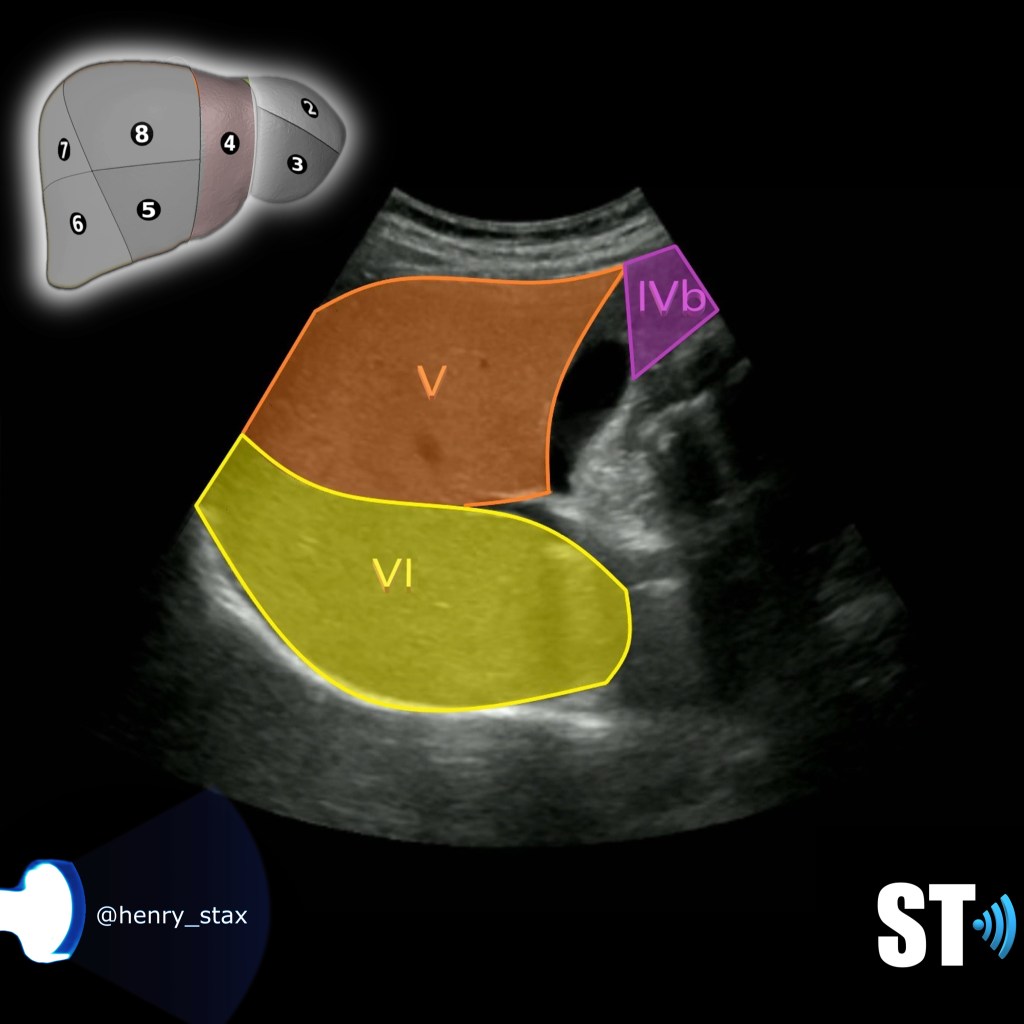

Segment IVb, V and VI

Segment IV is subdivided into IVa and IVb, superior and inferior and is located between the left and middle hepatic veins.

Segment V is inferior to the portal plane between the middle and right hepatic veins.

Segment VI is below the portal plane lateral to segment V/right hepatic vein.